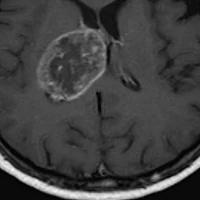

Veliki korak: Otkriven novi lek koji ubija samo ćelije raka, a ne oštećuje zdravo tkivo